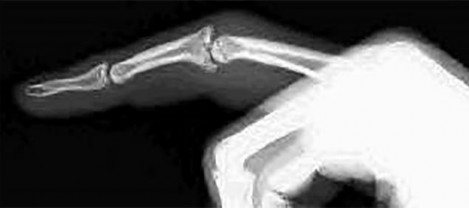

- الكسور: تُعد كسور عظام اليد والمعصم من الأسباب الشائعة للألم والخلل الوظيفي. تتضمن كسور السلاميات، العظام المشطية، عظام الرسغ (مثل كسر العظم الزورقي)، وكسور الكعبرة البعيدة (Distal Radius Fractures). قد تحدث هذه الكسور نتيجة السقوط على يد ممدودة، الإصابات الرياضية، أو حوادث السيارات.

- الخلوع: خلع المفاصل، مثل خلع المفصل المشطي السلامي (MCP) أو المفصل بين السلامي القريب (PIP)، يمكن أن يؤدي إلى ألم شديد وفقدان الوظيفة.

القيود في الحركة (Limited Range of Motion):

- صعوبة في ثني أو مد المفصل بالكامل: شائع في حالات التهاب المفاصل، بعد الكسور، أو بسبب تقلصات الأنسجة (مثل تقلص دوبويتران).

- تشوه في وضعية الأصابع أو الرسغ: مثل تشوه الرقبة البجعية (Swan-neck deformity) أو تشوه الأزرار (Boutonniere deformity) في التهاب المفاصل الروماتويدي أو بعد إصابات الأوتار.